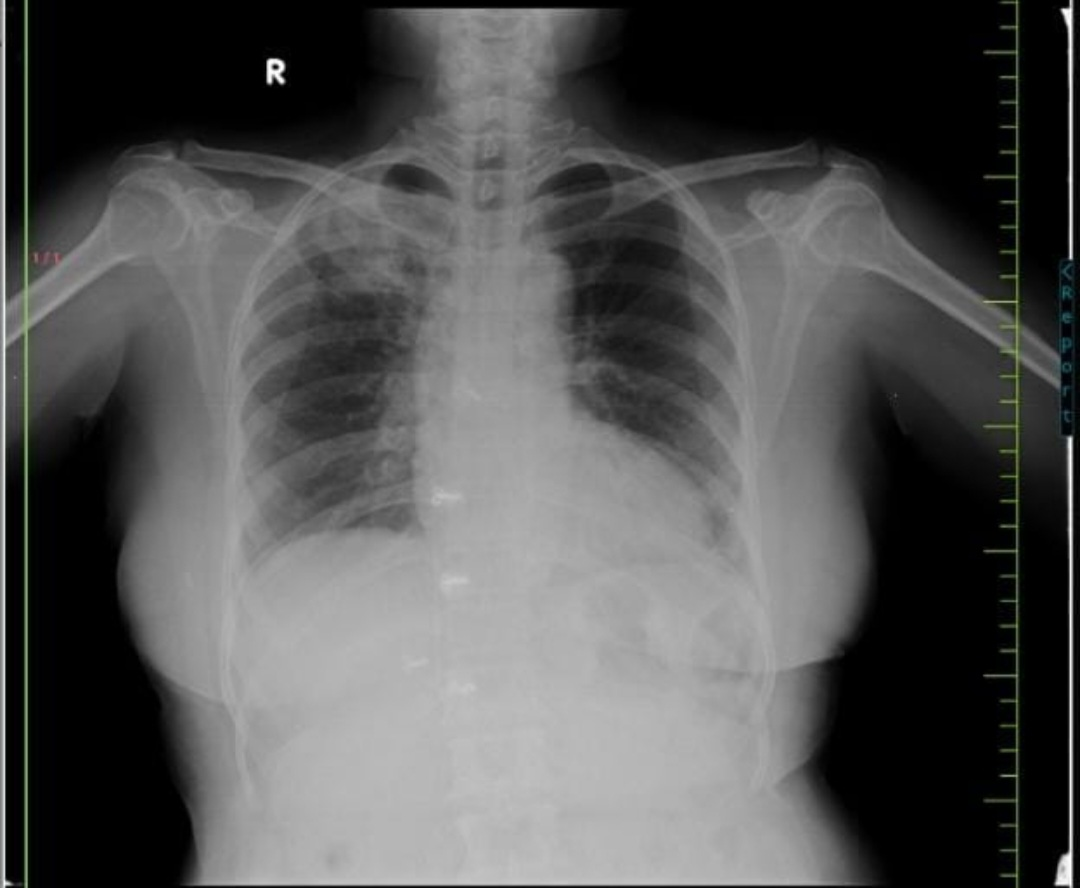

CHEST X RAY

DIAGNOSIS

? Community Acquired Pneumonia

? Pulmonary TB with rt upper lobe consolidation